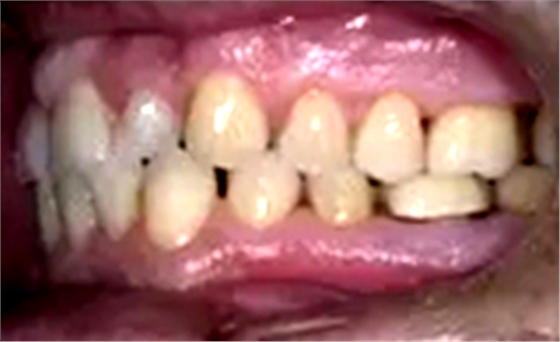

一位寻求改善微笑面容的43岁荷兰阿尔梅勒男子通过其全科牙医的介绍来到一家正畸医生的私人诊所,以纠正其错合畸形并在上颌前牙区域放置6个贴面。他属于牙形I类错合畸形,轻度骨性III类,覆合和覆盖减少以及前牙区存在间隙(图1)。

在最初的正畸咨询期间,拍摄了口内和口外照片连同一张全景片(图2),一张侧位头影片(图3)和正畸研究模型的海藻酸盐印模。